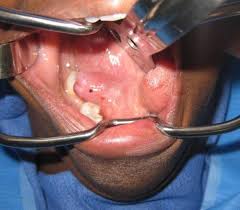

What is Ranula Surgery?

Ranula surgery involves removal of the cyst along with the affected salivary gland to prevent recurrence. It is a safe and effective procedure that provides long-term relief.

How is the Procedure Performed?

• Usually done under local or general anesthesia

• The cyst and associated gland are carefully removed

• Procedure is performed through the mouth (no external cuts in most cases)

• Surgery typically takes 30–60 minutes